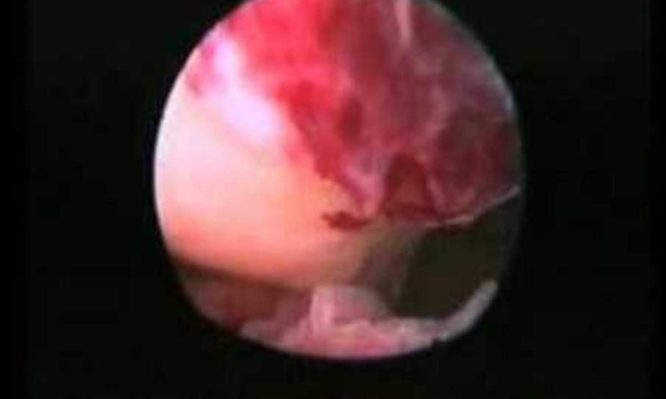

Για πρώτη φορά καταγράφεται η ανθρώπινη ωορρηξία.ΒΙΝΤΕΟ

Για να καταγραφεί η διαδικασία της ωορρηξίας το Ινστιτούτο Γονιμότητας και Εμβρυολογίας του Βελγίου χρησιμοποίησε διακολπικό ενδοσκόπιο. Στη συνέχεια οι επιστήμονες έκαναν μια μικρή τομή στο τοίχωμα του κόλπου για να παρατηρήσουν ευκολότερα και ευκρινέστερα την διαδικασία με το ενδοσκόπιο.

Μάλιστα οι ίδιοι υποστήριξαν ότι ήταν πολύ τυχεροί αφού την ημέρα της καταγραφής από την κάμερα υπήρχε η τέλεια ωορρηξία .